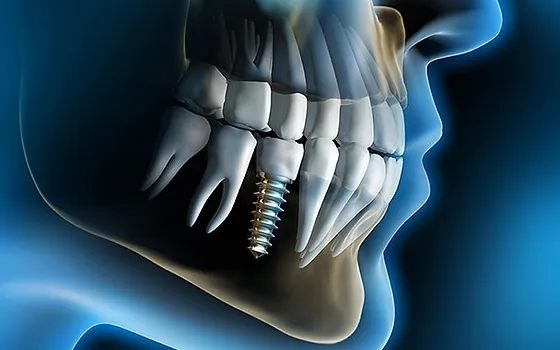

Ankara Üniversitesi Diş Hekimliği Fakültesini bitirdikten sonra aynı üniversitenin Ağız ,Diş ve Çene Cerrahisi Anabilim Dalı’nda doktora ve uzmanlık eğitimimizi tamamladık. 2007 yılında açtığımız kliniğimizde diş hekimliği genel tedavileri haricinde başlıca, çenelerdeki dişsiz boşlukların implant yerleştirilerek fonksiyon ve estetik görünümünün sağlanması , bu işlemi yaparken yetersiz kemik ve yumuşak dokuların arttırılması için hastanın kendinden alınan veya dışarıdan temin edilen kemik greftleri ile tedavi edilmesi, gömülü kalmış dişlerin ameliyat ile çıkartılması, çene kistleri ve tümörlerinin cerrahi tedavisi, çene eklemi ağrıları ve işlevsel bozukluklarının lazer tedavisi başta olmak üzere çeşitli tedavi yöntemleri ile giderilmesi, dil ve dudak sinirlerinin hasarına bağlı olarak gelişen uyuşukluğun ve iyileşmeyen ağız içi yaralarının düşük akım lazer metodu ile tedavi edilmesi, çenelerdeki gelişimsel bozuklukların ortognatik cerrahi ile estetik olarak düzeltme tedavileri verilmektedir.